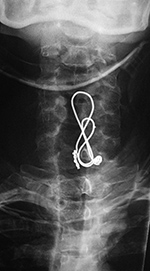

| Odontoid fixation screw AP view |

Odontoid fixation screw lateral view |

Posterior cervical spine clamp |

Odontoid fracture fixation |

Postoperative lateral radiograph of the cervical spine. There is fixation of an odontoid base fracture by an odontoid screw and a sublaminar wire between C1 and C2. There are also skin staples and a surgical drain in the posterior aspect of the neck |

| Odontoid Fracture Fixation |